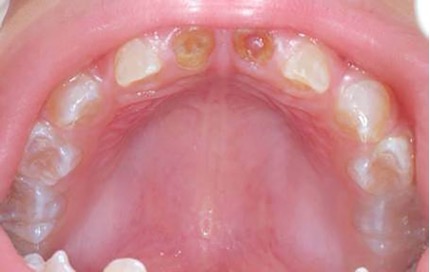

El examen clínico intraoral reveló alteración de la estructura y color de las piezas primarias, atrición y pérdida de la dimensión vertical (Figura 2). Radiográficamente se observó la presencia de coronas con marcada constricción cervical y raíces cortas (Figura 3). Presentaba alto riesgo cariogénico, por la presencia de lesiones de caries activas y dos restos radiculares, sumado a la anomalía estructural de la dentina (riesgo biológico específico) y bajo riesgo gingivoperiodontal. El riesgo socio-económico era alto por provenir de una familia con marcadas limitaciones económicas. Luego de la anamnesis, examen clínico y radiográfico, e interconsulta con el médico de cabecera se estableció el diagnóstico de DI Tipo I asociado a OI tipo I. Se planificó un tratamiento integral y preventivo con los objetivos de devolver forma y función, y proteger y evitar el desgaste de los tejidos conductas que pudieran interferir con el tratamiento.

Figura 2: Examen clínico intraoral del maxilar superior e inferior y vista anterior. Año 2007